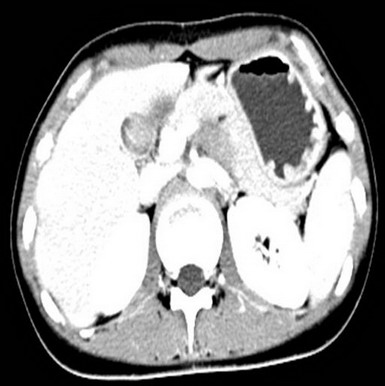

2009.6.23 腹部CT

腹膜后占位,性质待定,十二指肠局部穿透伴炎性包裹,十二指肠水平段梗阻,近端积液扩张,肝小囊肿(胰体后下方见不规则软组织密度影,大小约48mm*33mm,其内见气体密度影,增强扫描静脉期肿块明显不均匀强化,CT值约30HUPS 86HUCE,病变与十二指肠水平段、升段及胰腺分界不清,十二指肠水平段明显变窄,胃及近端十二指肠明显积液扩张。)